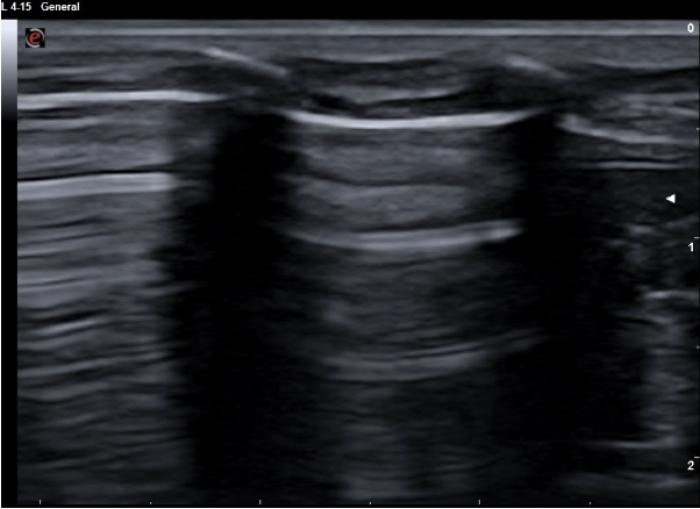

Pulso pulmonar

Es la transmisión del latido cardíaco a través del tejido pulmonar. Aunque es considerado un movimiento normal dentro de la exploración pulmonar con ultrasonido, especialmente en regiones próximas al corazón, lo cierto es que cuando se visualiza con facilidad es posible que exista una mayor consolidación pulmonar sin llegar a la superficie pleural, el aumento de peso del lóbulo transmite mejor dicho movimiento y lo hace más evidente. Su visualización excluye el neumotórax en el área observada.

Puede evaluarse tanto en modo M como en modo B (Figura 7) (Vídeo 3).